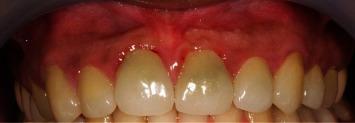

Iatrogenic root perforation presents a significant management challenge for clinicians as it may seriously harm the periodontium. More specifically, perforations occurring relative to the crestal bone have a poor prognosis even after repair due to their proximity to the gingival tissues. The current literature reports the use of various materials for root perforation repair including calcium hydroxide, glass ionomer cement, amalgam, and mineral trioxide aggregate (MTA), to name a few. This case report describes the clinical management of a cervical perforation that occurred on the maxillary central incisor. The perforated area was initially repaired with MTA but failed after one year, which resulted in an active lesion at the midlabial aspect of the tooth. The case was subsequently treated using a resin-modified glass ionomer cement (Geristore®) and deepithelialized free gingival graft (DGG). There were favorable clinical and radiographic outcomes at 1-, 3-, and 5-year follow-up. The use of DGG, however, led to some late complications such as gingival cul-de-sac and color discrepancy, which were later resolved with gingivoplasty and frenectomy. We thus conclude that Geristore® has the potential to be a better repair material than the existing ones for crestal and subcrestal root perforations.

医源性牙根穿孔给临床医生带来了重大的治疗挑战,因为它可能会严重损害牙周组织。更具体地说,相对于牙槽嵴顶骨发生的穿孔,即使在修复后预后也很差,因为它们靠近牙龈组织。目前的文献报道了使用多种材料进行牙根穿孔修复,包括氢氧化钙、玻璃离子水门汀、汞合金和三氧化矿物凝聚体(MTA)等等。本病例报告描述了上颌中切牙发生的颈部穿孔的临床治疗情况。穿孔区域最初用MTA修复,但一年后失败,导致牙齿唇面中部出现活动性病变。该病例随后使用树脂改性玻璃离子水门汀(Geristore®)和去上皮游离龈瓣(DGG)进行治疗。在1年、3年和5年的随访中,临床和影像学结果良好。然而,DGG的使用导致了一些晚期并发症,如牙龈盲袋和颜色差异,后来通过牙龈成形术和系带切除术得到了解决。因此,我们得出结论,对于牙槽嵴顶和牙槽嵴下牙根穿孔,Geristore®有可能成为比现有材料更好的修复材料。